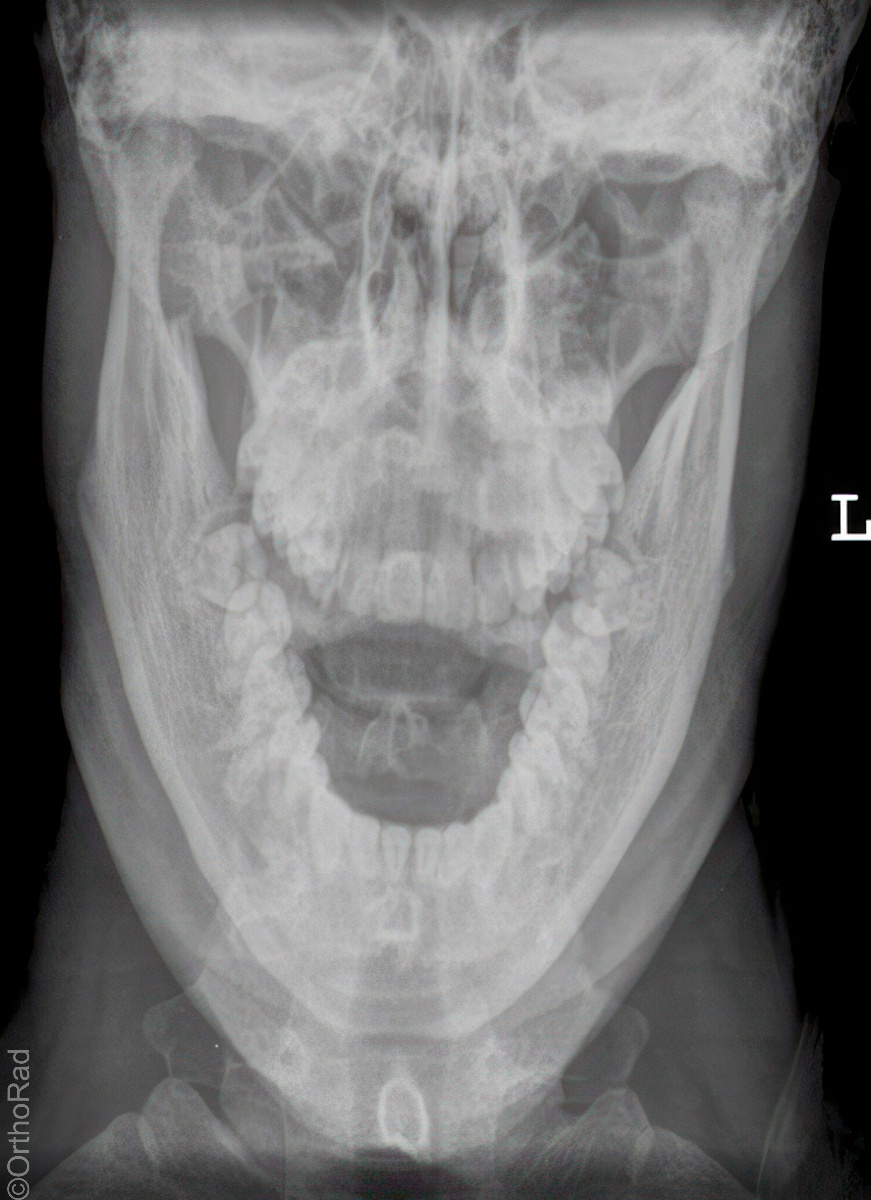

Unterkiefer nach Clementschitsch

Technik

• FDA: 1,15 m

• Ausgangsformat: 18/24 hoch

• mit Raster

• Röhrenkippung: 15° caudo-cranial

Lagerung

sitzt aufrecht und gerade mit dem Gesicht zum Stativ

Kopf gerade

Kinn stark anziehen lassen

Stirn dem Stativ anliegt

Mund maximal öffnen

Zentralstrahl

Im Winkel von mindestens 15° caudo-cranial okzipitomental. Längsstrahl verläuft durch die Medianebene. Querstrahl unterhalb des Occiputs auf Nasenwurzel. Achtung! Bei Röhrenkippung auf Zentrierung achten.

Anmerkung

Vollständige Darstellung des Unterkiefers und gute Beurteilung der Kiefergelenke. Bei Kiefergelenk Fragestellung:

1. Aufnahme mit geöffneten Mund

2. Aufnahme mit geschlossenem Mund

Qualitätskriterien

Übersichtliche Darstellung des gesamten Unterkiefers mit seitengleich gut einsehbaren Kiefergelenken